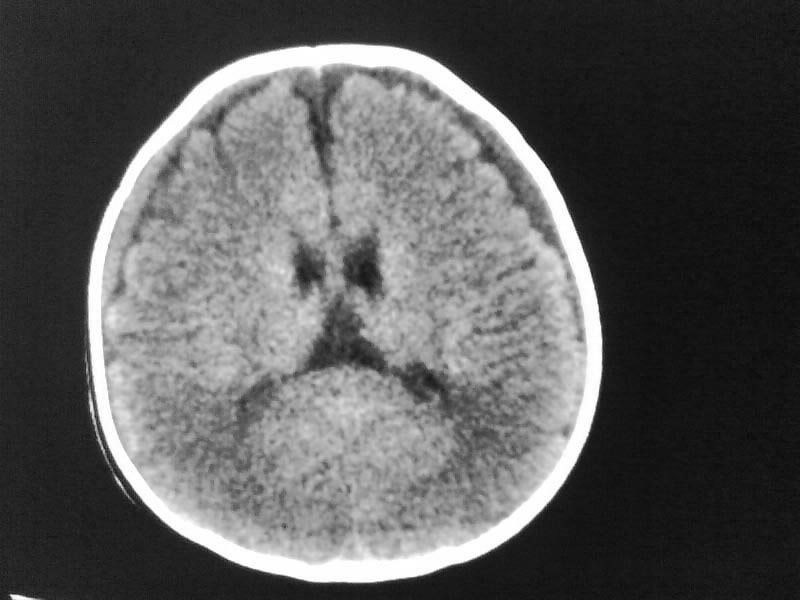

以下是引用小初学者在2009-4-15 10:26:00的发言:[br]考虑右侧额顶部硬膜下血肿。

以下是引用随光逐影在2009-4-15 17:59:00的发言:[br]1)右侧额颞顶部硬膜下血肿。2)外部性脑积水。